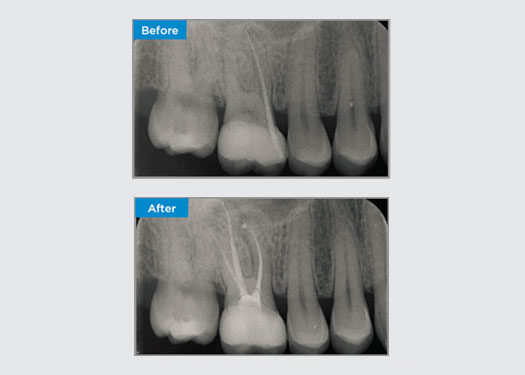

Le patient s’est présenté avec une parodontite apicale asymptomatique sur la dent 34. Sur la radiographie préopératoire, la dent 34 présentait deux racines visibles. Cependant, un balayage CBCT a confirmé qu’il s’agissait d’une prémolaire à trois racines et que les canaux se divisaient en trois au milieu de la racine. Une sélection minutieuse des limes est essentielle pour cette dent délicate.

Dr Jack Lin, Endodontiste, Sydney, NSW Australie

Dans cette situation, la préservation de la structure de la dent/racine est essentielle pour réduire le risque de déviation, de déplacement, de fermeture, de perforation et de fracture de la racine. La sélection des cas, le diagnostic et la planification du traitement préalable sont importants. Le choix de la lime endodontique en fonction de sa flexibilité, de son efficacité et du respect de l’anatomie naturelle de la racine est essentiel.